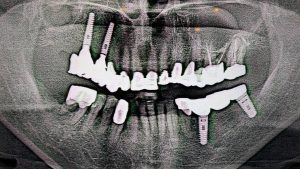

奥歯の欠損や食いしばりの習慣により、右側顎関節が変異した症例

【患者様に関する情報】 ・78歳の男性。昭和30年からずっと通っていただいている方。 ・もともと奥歯があったが、歯槽膿漏が…